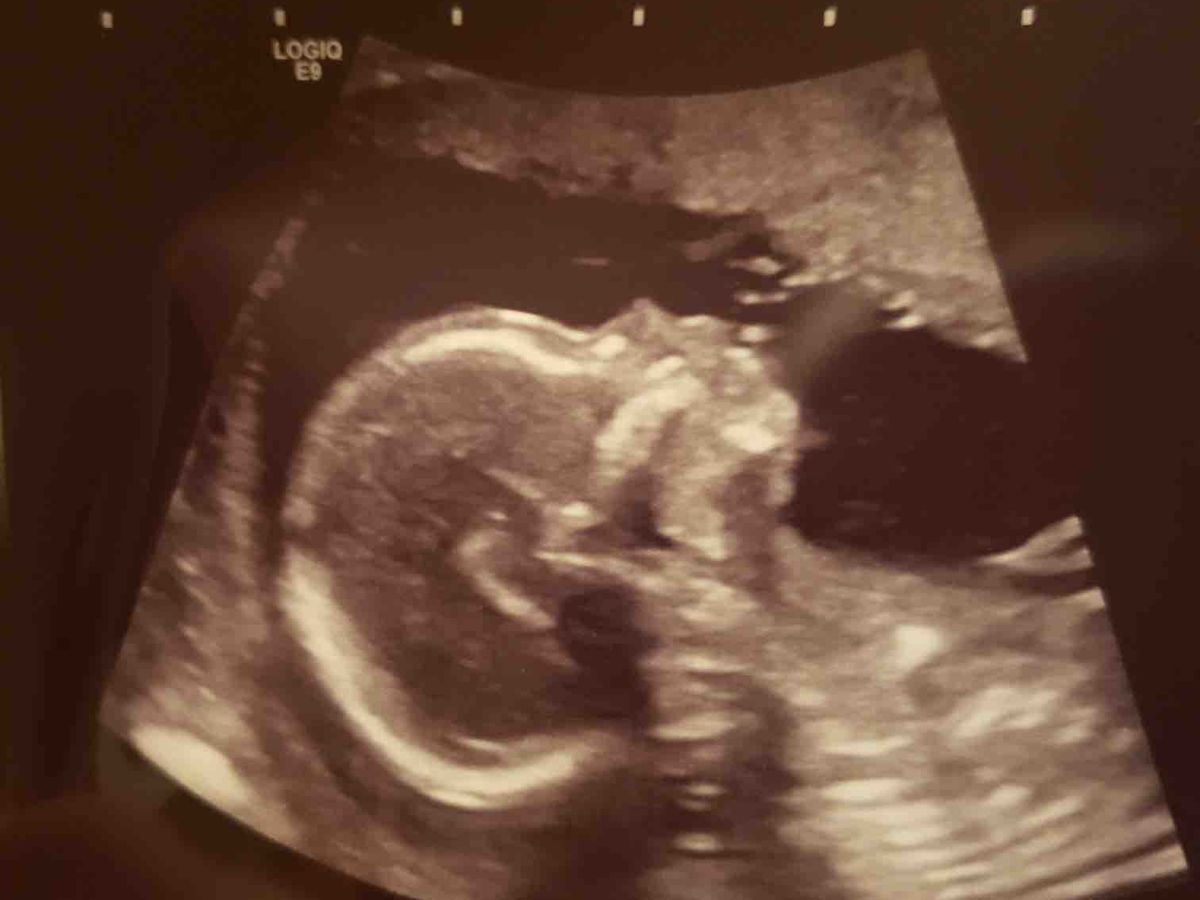

Ultimately- we chose grace and acceptance. We love him so much and know that he is going to be a huge blessing to our family and to everyone he meets. Our entire world changed with one ultrasound. We are trying to stay as positive as we can and see where this new adventure leads us.